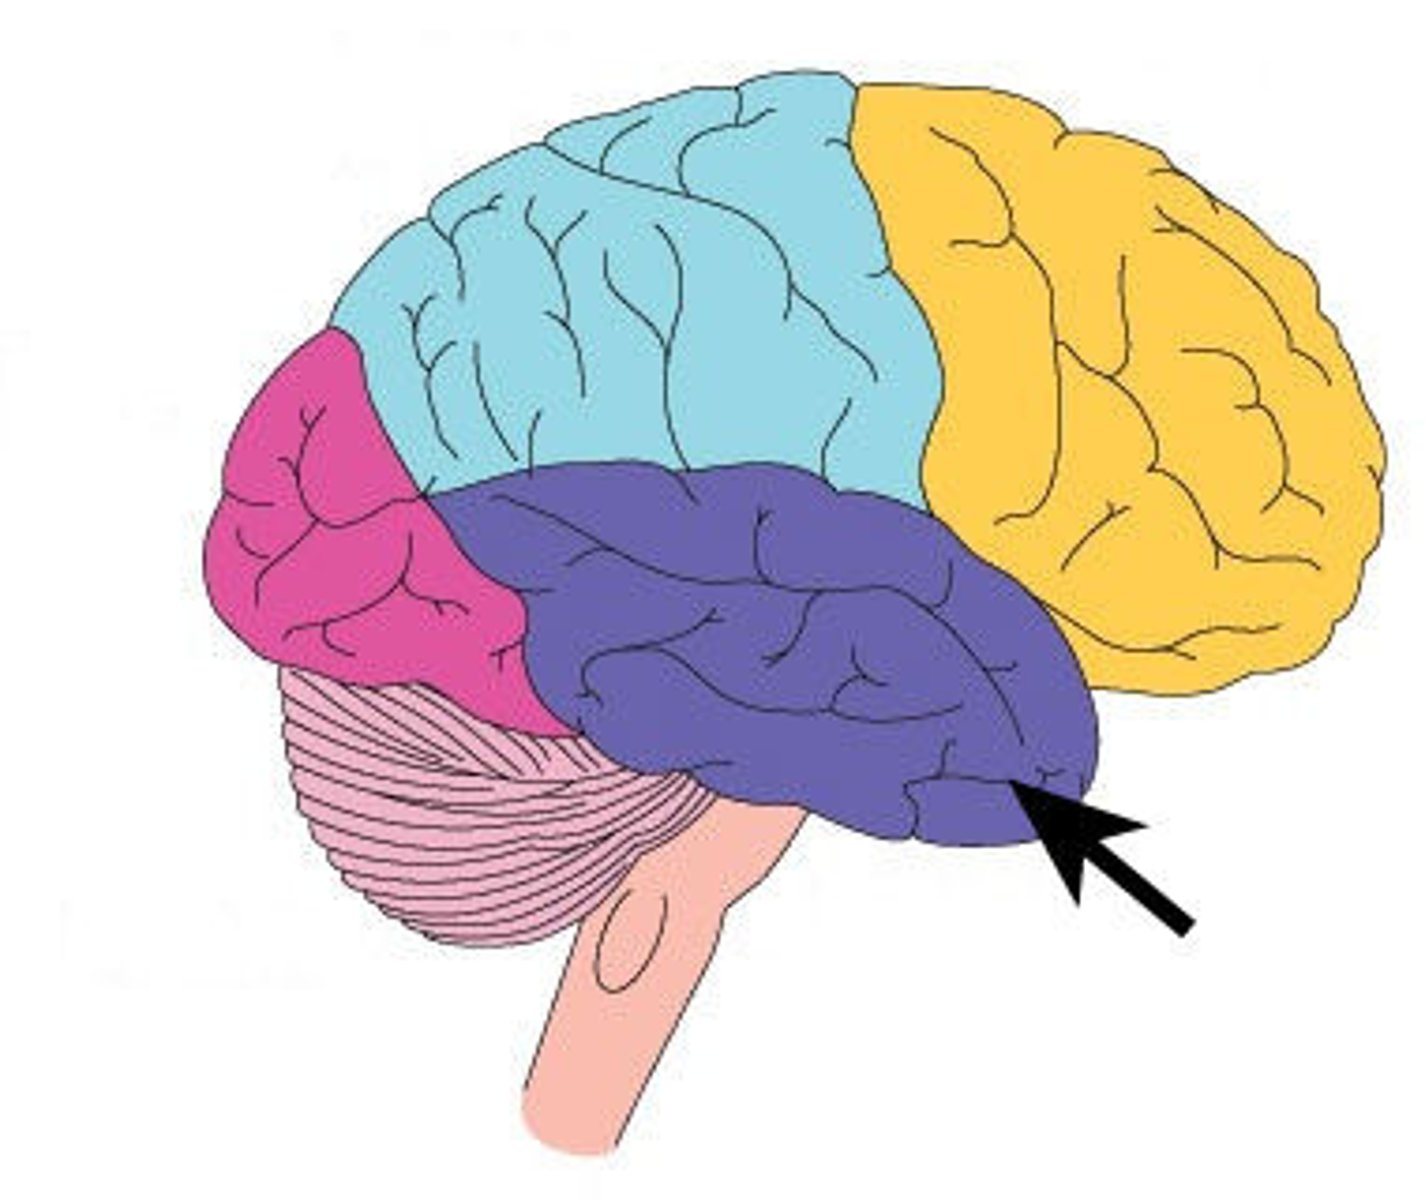

frontal lobe

Regions of the cerebrum involved in:

•Voluntary motor functions

•Motor control, concentration, verbal communication, decision making, planning, personality

parietal lobe

Region of the cerebrum that:

•receives and integrates general sensory information (shape, texture), taste and some visual processing

occipital lobe

•primary visual center of brain (vision and visual memories)

temporal lobe

Regions of the cerebrum that:

•contains areas for hearing, smell, learning, memory, and some aspects of vision and emotion

central sulcus

separates frontal and parietal lobes

lateral sulcus

Separates temporal lobe from parietal and frontal lobes